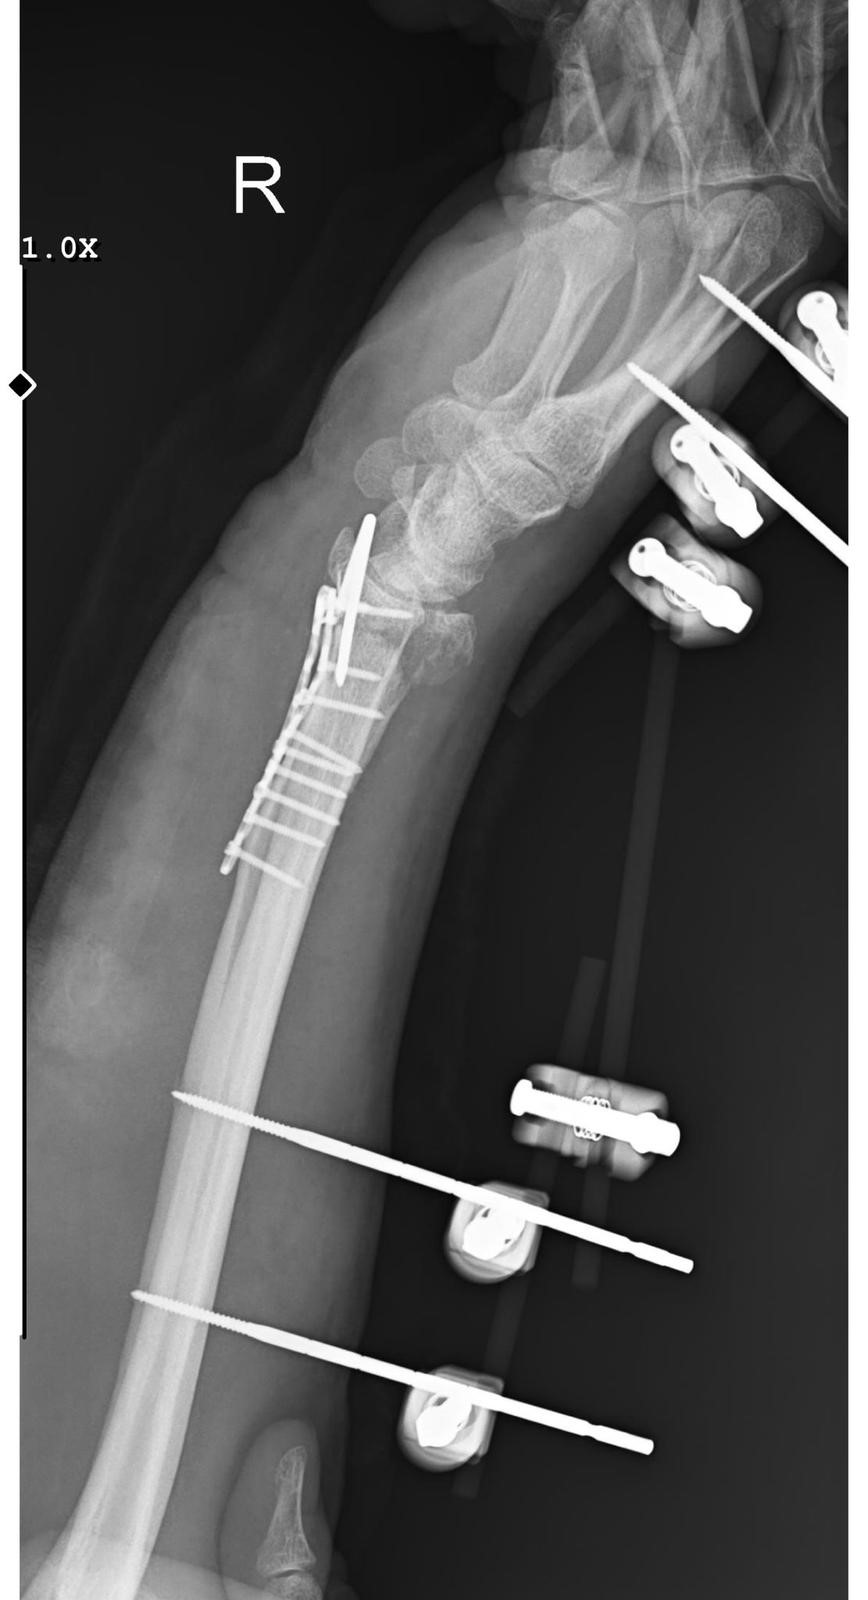

"BİLEĞİMDE 15 DİKİŞ VE 11 PLATİN VAR

Yasin Arslantaş, "Sabah apartmandan çıkış yaptığım sırada arkamdan 9 köpeğin geldiğini gördüm. Saldırgan haldelerdi. Bana saldırmak üzerelerdi. Kaçmaya çalışırken ayağım kaydı ve düştüm. Bileğimde 15 dikiş ve 11 platin var. İki ay boyunca kolum bu halde kalacak ve ardından da yine 2 buçuk ay fizik tedavi süreci olacak. Doktorlar his ve hareket kaybımın olacağını söylediler. Bileğimden büyük kemiğin kırılmasından dolayı zorlu bir süreç geçiriyorum. 3 saatlik bir ameliyat geçirdim" dedi.